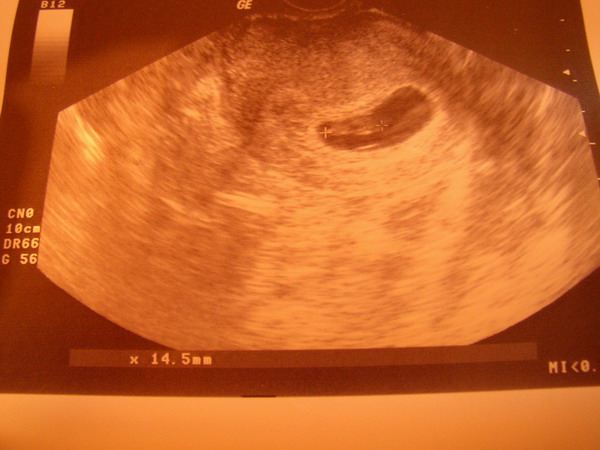

Gyönyörű képek! Ugye milyen megható a szívhangot hallgatni